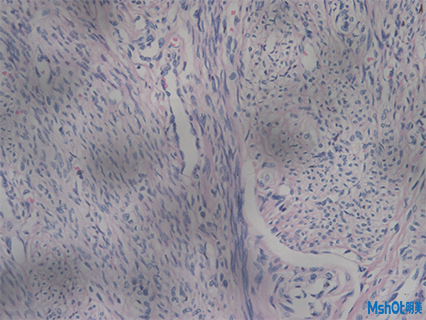

病理切片取一定大小的病變組織,用病理組織學(xué)方法制成病理切片。病理切片是透明的,在顯微鏡下能夠觀察到組織的形態(tài),搭配顯微鏡相機(jī)可對(duì)觀察到的形態(tài)效果圖進(jìn)行保存對(duì)比,拼接等操作,通過(guò)病變的發(fā)生發(fā)展過(guò)程,作出病理診斷。

病理切片

近日,深圳某醫(yī)療科技公司在網(wǎng)上找到我們,客戶(hù)已有一臺(tái)奧林巴斯倒置顯微鏡IX71,需要配一套高像素顯微鏡相機(jī)拍病理切片和熒光切片,深圳區(qū)域工程師根據(jù)老師實(shí)際需求推薦了明美科研級(jí)顯微鏡相機(jī)MSX2,這款顯微鏡相機(jī)采用大靶面高性能的成像芯片,設(shè)計(jì)USB3.0數(shù)據(jù)傳輸接口,具有高分辨率、顏色還原準(zhǔn)確和高靈敏度的特點(diǎn),其色彩表現(xiàn),是液基細(xì)胞分析、免疫組化、骨髓細(xì)胞分析等對(duì)顏色要求高的病理診斷的理想工具。此外在明暗場(chǎng)、相襯、偏光、DIC、熒光成像等領(lǐng)域同樣適用。